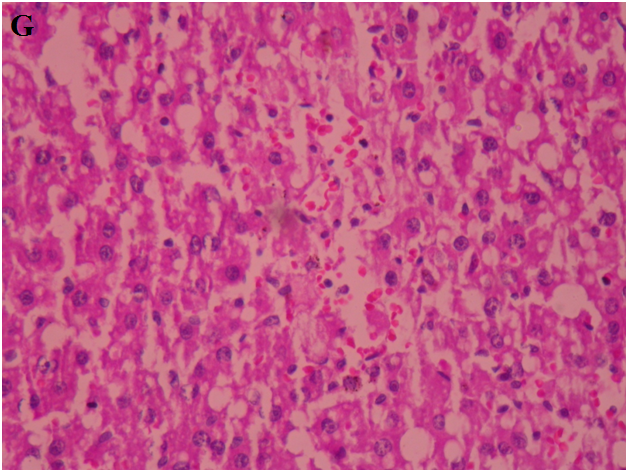

Normal hepatic cell arrangement was observed in the normal liver. Central vein, portal tract, and normal kupffer cells showed no inflammation (fig. 6A). In CCl4 treated group hepatocytes exhibited large degeneration of fatty cells, congestion of central vein and sinusoid, spotty necrosis, focal hemorrhage, ballooning and inflammation of hepatic cells (fig. 6B). In standard silymarin (100 mg/kg) treated group the hepatic globular structure was found to be normal. Mild central vein and sinusoidal congestion were noticed. Regeneration of hepatocytes was also found (fig. 6C). A4EA treated livers (50 mg/kg) exhibited normal rearrangement of hepatocytes surrounding the necrosis and fatty vacuoles (fig. 6D). A4EA treated livers (100 mg/kg) showed mild congestion of central vein and sinusoid. Mild inflammation and focal hemorrhage were seen, whereas no degeneration and ballooning of hepatic cells was observed (fig. 6E). A4nB (50 mg/kg) treated livers showed decreased inflammation of hepatocytes. Mild ballooning and degeneration of injured liver were restored (fig. 6F). A4nB (100 mg/kg) treated livers also showed regeneration of hepatocytes with mild inflammation and ballooning (fig. 6G).

G. A4nB(100 mg/kg)

Fig. 6: Histopathological sections of liver with CCl4 induced hepatotoxicity: A. Normal liver, B. CCl4 induced rat liver, C. Silymarin treated rat liver, D. A4EA (50 mg/kg), E. A4EA(100 mg/kg), F. A4nB(50 mg/kg), G. A4nB (100 mg/kg)

Normal hepatic cell arrangement was seen in the normal liver as compared to CCl4 group as hepatocytes exhibited large degeneration of fatty cells, congestion of central vein and sinusoid, spotty necrosis, focal hemorrhage, ballooning and inflammation of hepatic cells. A4EA (50 mg/kg and 100 mg/kg) showed normal rearrangement of hepatocytes round the necrosis and fatty vacuoles, with mild congestion of central vein and sinusoid. A4nB (50 mg/kg and 100 mg/kg) showed decreased inflammation of hepatocytes. Mild ballooning and degeneration of injured liver were restored. These observations showed that A4EA and A4nB (50 mg/kg and 100 mg/kg) reversed the toxic effects of CCl4 on hepatic architecture.